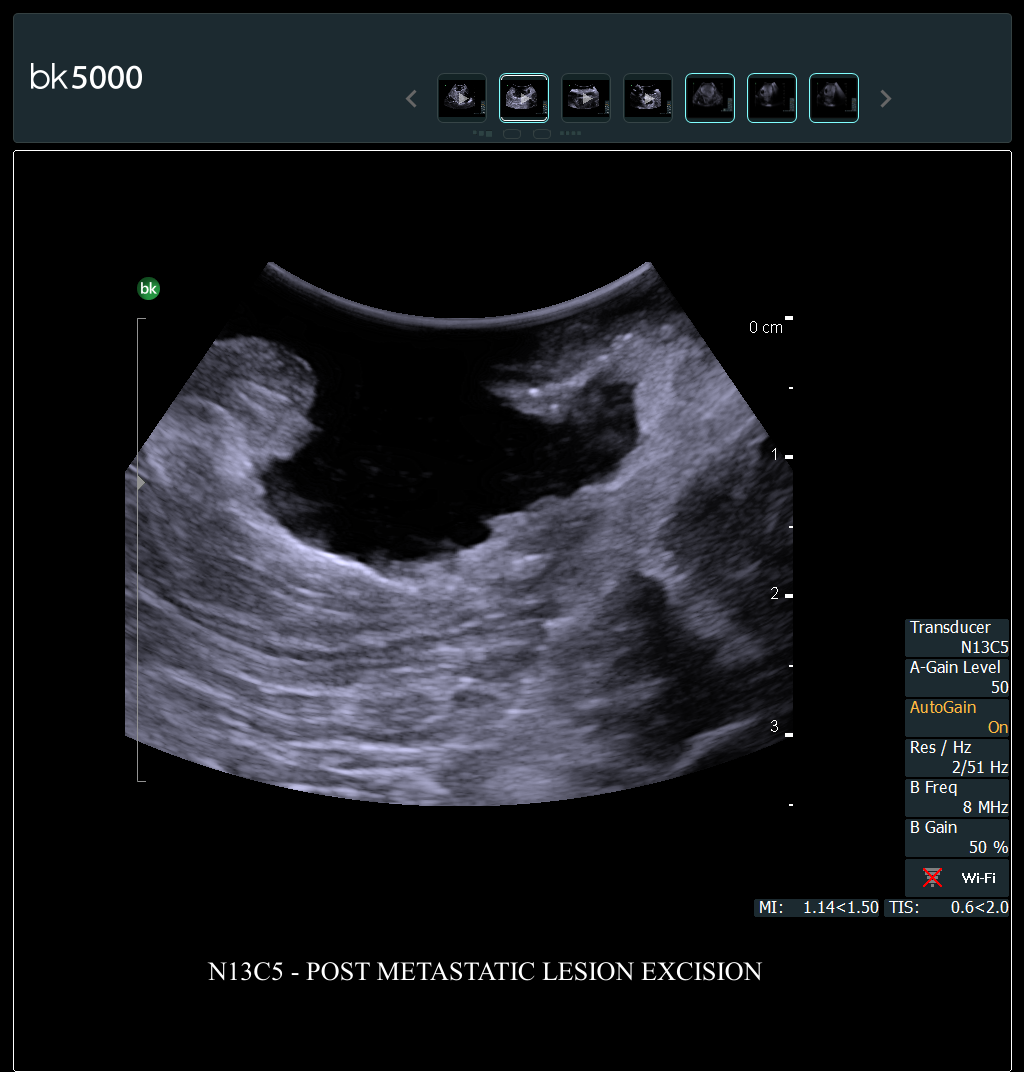

Ultrasound can improve neurosurgical procedures by helping you navigate and identify lesions and anatomical structures in real-time. This is particularly important as the data obtained from a preoperative CT or MRI scan can be outdated at the time of surgery. The bk5000 neurosurgical system provides the highest quality images that allow you to clearly see the margins of a lesion and to determine the best course of action. Using advanced graphics processing technology, this powerful system provides immediate, auto-optimized images that allow you to see the information you need, faster.

The specialized, high-resolution, sterilizable neurosurgery transducers enable you to obtain detailed images of the brain and spinal cord. They have a convenient Smart™ button that lets you activate the transducer, then freeze, store or print the images at the press of a button. Disposable, easy-to-use needle guides assist with targeting lesions.